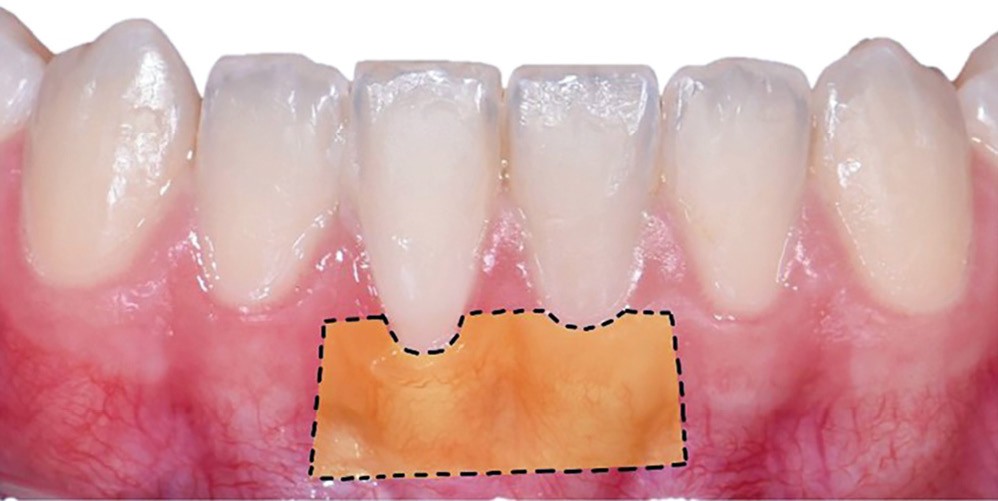

La greffe épithélio-conjonctive (GEC) [7, 8] consiste au remplacement du tissu parodontal existant par un greffon épithélio-conjonctif dont l’indication principale est l’augmentation en hauteur et en épaisseur du tissu kératinisé (fig. 2). Elle peut aussi être utilisée dans le recouvrement radiculaire (avec des résultats en termes de recouvrement inférieurs à ceux des techniques de greffe de conjonctif enfouie), l’aménagement des crêtes édentées, l’aménagement péri-implantaires [9, 10] (fig. 3), ou en association avec un traitement ortho-parodontal [11]. Le principal défaut de cette technique est son aspect inesthétique ; elle sera donc réservée à des zones non visibles comme les incisives mandibulaires ou les zones postérieures.

De nombreuses techniques de lambeaux déplacés latéralement, lambeaux déplacés coronairement (fig. 4), enveloppes ou tunnels (fig. 5) ont fait l’objet de publications et présentent des résultats quasi identiques en termes de recouvrement. Leurs points communs sont un recouvrement complet du greffon, une dissection en épaisseur partielle suffisante pour assurer un positionnement du lambeau sans tension et l’absence (quand cela est possible) d’incision de décharge. Le choix d’une ou l’autre technique dépend surtout de l’expérience du praticien et de la quantité de tissu disponible apicalement ou latéralement.